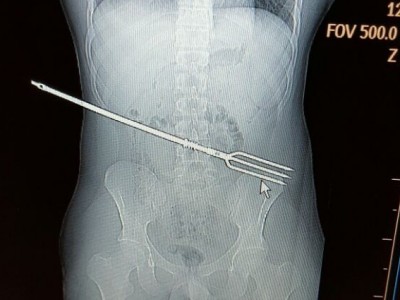

אאוץ': שלפו צלצל מבטנו של צעיר טברייני

מקרה בהול ולא שגרתי הגיע ביום שישי האחרון לבית החולים פוריה: "בעזרת לפרוסקופיה הכנסנו מצלמה לחלל הבטן ואז התברר כי למרבה המזל, הצלצל לא פגע באיברים הפנימיים", סיפר ד"ר מילאד